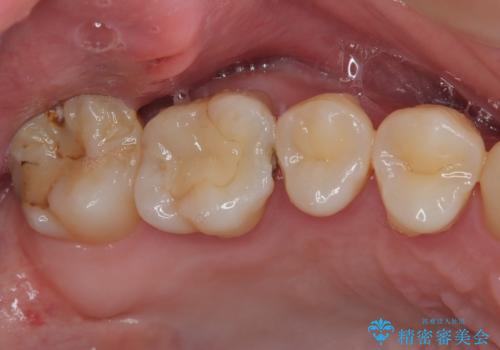

- 他院で矯正治療前後に処置を行った歯が痛むとのことで来院された患者様です。

下顎大臼歯は根管治療がされている歯が咬合時に痛みを感じ、上顎の大臼歯2歯は冷たいものがしみる状態でした。

まずはしみる上顎の歯を仮歯に置き換え、その後下顎の根管治療を行った上で、異常が認められなければオールセラミッククラウンにて補綴治療を行うこととしました。